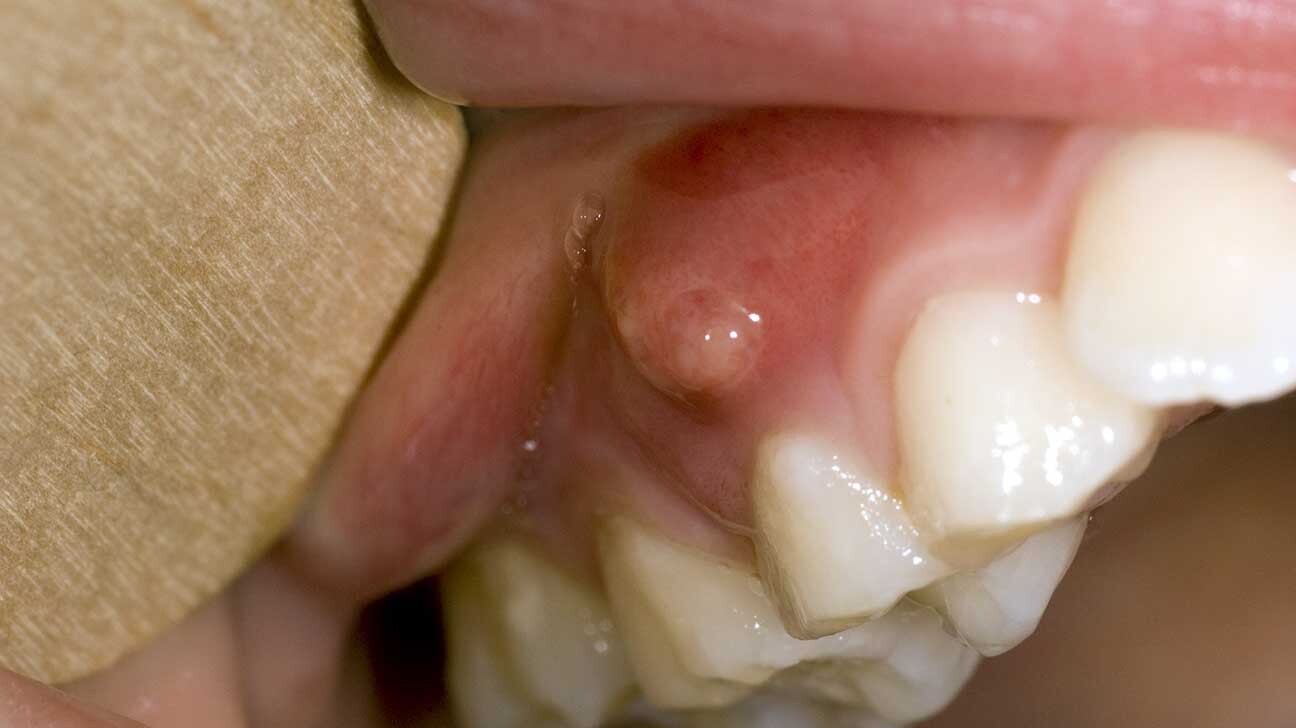

An Abscess – An extremely sensitive, painful bump on your gums that looks like a pimple is likely an abscess. An abscess is due to a bacterial infection and occurs as pus collects under the gum, forming a bump or boil.

There are different types of abscesses, including a periodontal abscess, which is usually caused by periodontitis (advanced gum disease), and a periapical abscess, which is an infection at the tip of your tooth’s root from tooth decay or an injury. A periapical abscess usually presents as a bump on the gums above or below the affected tooth.

It’s important to have an abscess evaluated and treated. It won’t go away on its own. While it can drain and provide temporary relief, the infection will still be present and can spread to the jaw and supporting tissues. In rare cases, a dental infection can reach the brain and cause serious health complications.

Treatment for an abscess will involve treating the infection, whether through periodontal care or a root canal, and, sometimes, antibiotics. We might also drain the abscess to give you immediate relief.